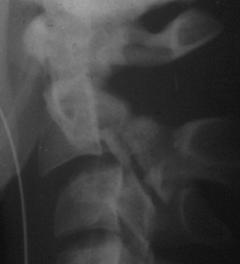

Fractura Jefferson Fractura spanzuratului

Aspect CT

Fractura spanzuratului Fractura anterioara C4 Fractura C5 in lacrima in flexie

"in lacrima"

Fractura C5 "in lacrima" in extensie Luxatie fatetara